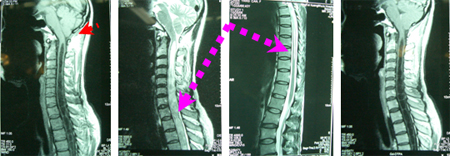

女性,40岁,双上肢麻木、无力5年,伴走路不稳。查体:双上肢近端肌力3级、远端2级,双手鱼际肌萎缩明显,稍显爪形手畸形,针刺痛觉减退区呈片状分布。影像学资料显示:后颅窝狭小、拥挤,小脑扁桃体下疝,伴发巨大脊髓空洞、分隔状、下级达T9水平,没有增强表现(区别于肿瘤)。

手术操作:枕颈减压的枕骨鳞部骨窗大小约为3×2cm大小、寰椎后弓打开约一横指宽,不损伤蛛网膜的情况下、“Y”形剪开硬脑膜,为防止蛛网膜粘连、以人工神经补片做枕大池重建,进一步使颅颈交界区软性空间充分扩大,空洞穿刺引流出积存脑脊液约7ml。

术后肢体麻木改善,走路稳,术后1年半肢体肌力和肌萎缩好转。